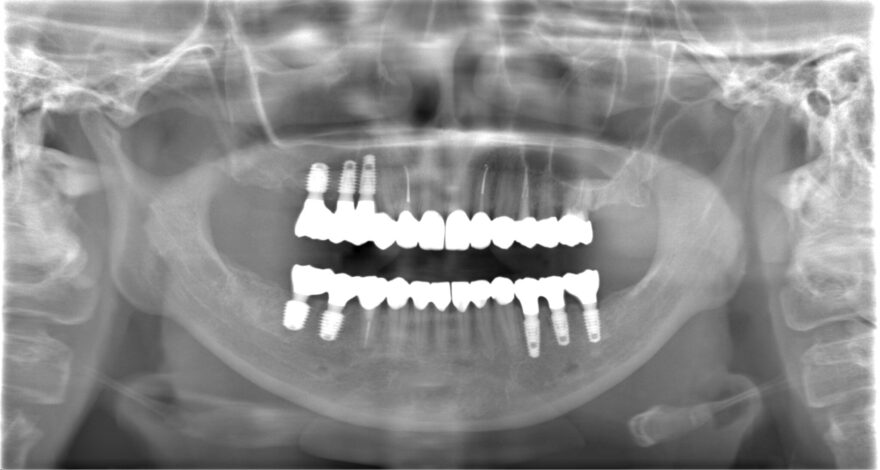

奥歯がなくて噛めない上に顎まで痛い:50代女性

Before

AFTER

治療内容

困った時に、その場限りの治療でしのいできたものの、いよいよ顎まで痛くなってしまい、当院を受診されました。

7本のインプラント治療と18本のセラミック治療で、顎関節とのバランスまで考慮した機能的な噛み合わせを再建しました。

治療期間

1年

費用

前歯インプラント2本→990,000円(税込)

《1本あたり495,000円(税込)》

奥歯インプラント5本→2,200,000円(税込)

《1本あたり440,000円(税込)》

前歯プレミアムセラミック10本→1,650,000円(税込)

《1本あたり165,000円(税込》

奥歯プレミアムセラミック8本→114,4000円(税込)

《1本あたり143,000円(税込)》

ファイバーコア6本→132,000円(税込)

《1本あたり22,000円(税込)》

前歯精密根管治療2本→220,000円

《1本あたり110,000円(税込)》

咬合再構成(全ての仮歯代とデジタルデザイン含む)25本→825,000円

《1本あたり33,000円(税込)》

総額 7,161,000円(税込)